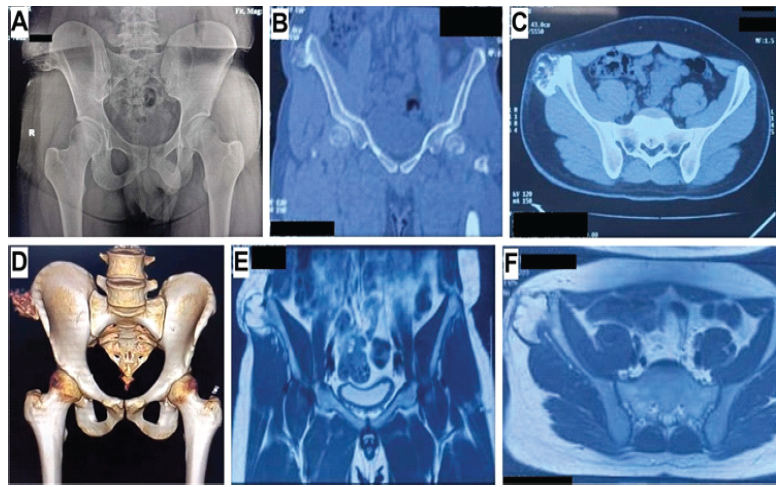

A pelvic radiograph revealed skeletal maturity (Risser grade 5). The presence of a radio-opaque, rounded mass arising from the outer table of the anterior third of the right iliac wing just posterior to the ASIS was noted (Fig. 4).

Figure 4: Pre-operative radiologic evaluation of the second patient. (a) Anteroposterior radiograph of the pelvis with both hips, (b) computed tomography image of the pelvis, coronal section, (c) computed tomography image of the pelvis, transverse section, (d) computed tomography image of the pelvis, three-dimensional reconstruction, (e) magnetic resonance imaging of the pelvis, coronal section, and (f) magnetic resonance imaging of the pelvis, transverse section (Potential patient identifiers have been blacked out).

Computed tomography and MRI were suggestive of an osteochondroma; a well-defined pedunculated lesion arising from and continuous with the underlying ilium was noted (Fig. 4). The mass was globular and measured approximately 4.5 × 3.6 × 4.2 cm. Its pedicle was 2 cm wide. A thin cartilaginous cap measuring a maximum of 6 mm in thickness, with no focal thickening or heterogeneity, was noted. The iliotibial band was displaced laterally due to the mass. No adjacent collection or bursa formation was noted, nor were there signs of adjacent neurovascular compression or pelvic lymphadenopathy.